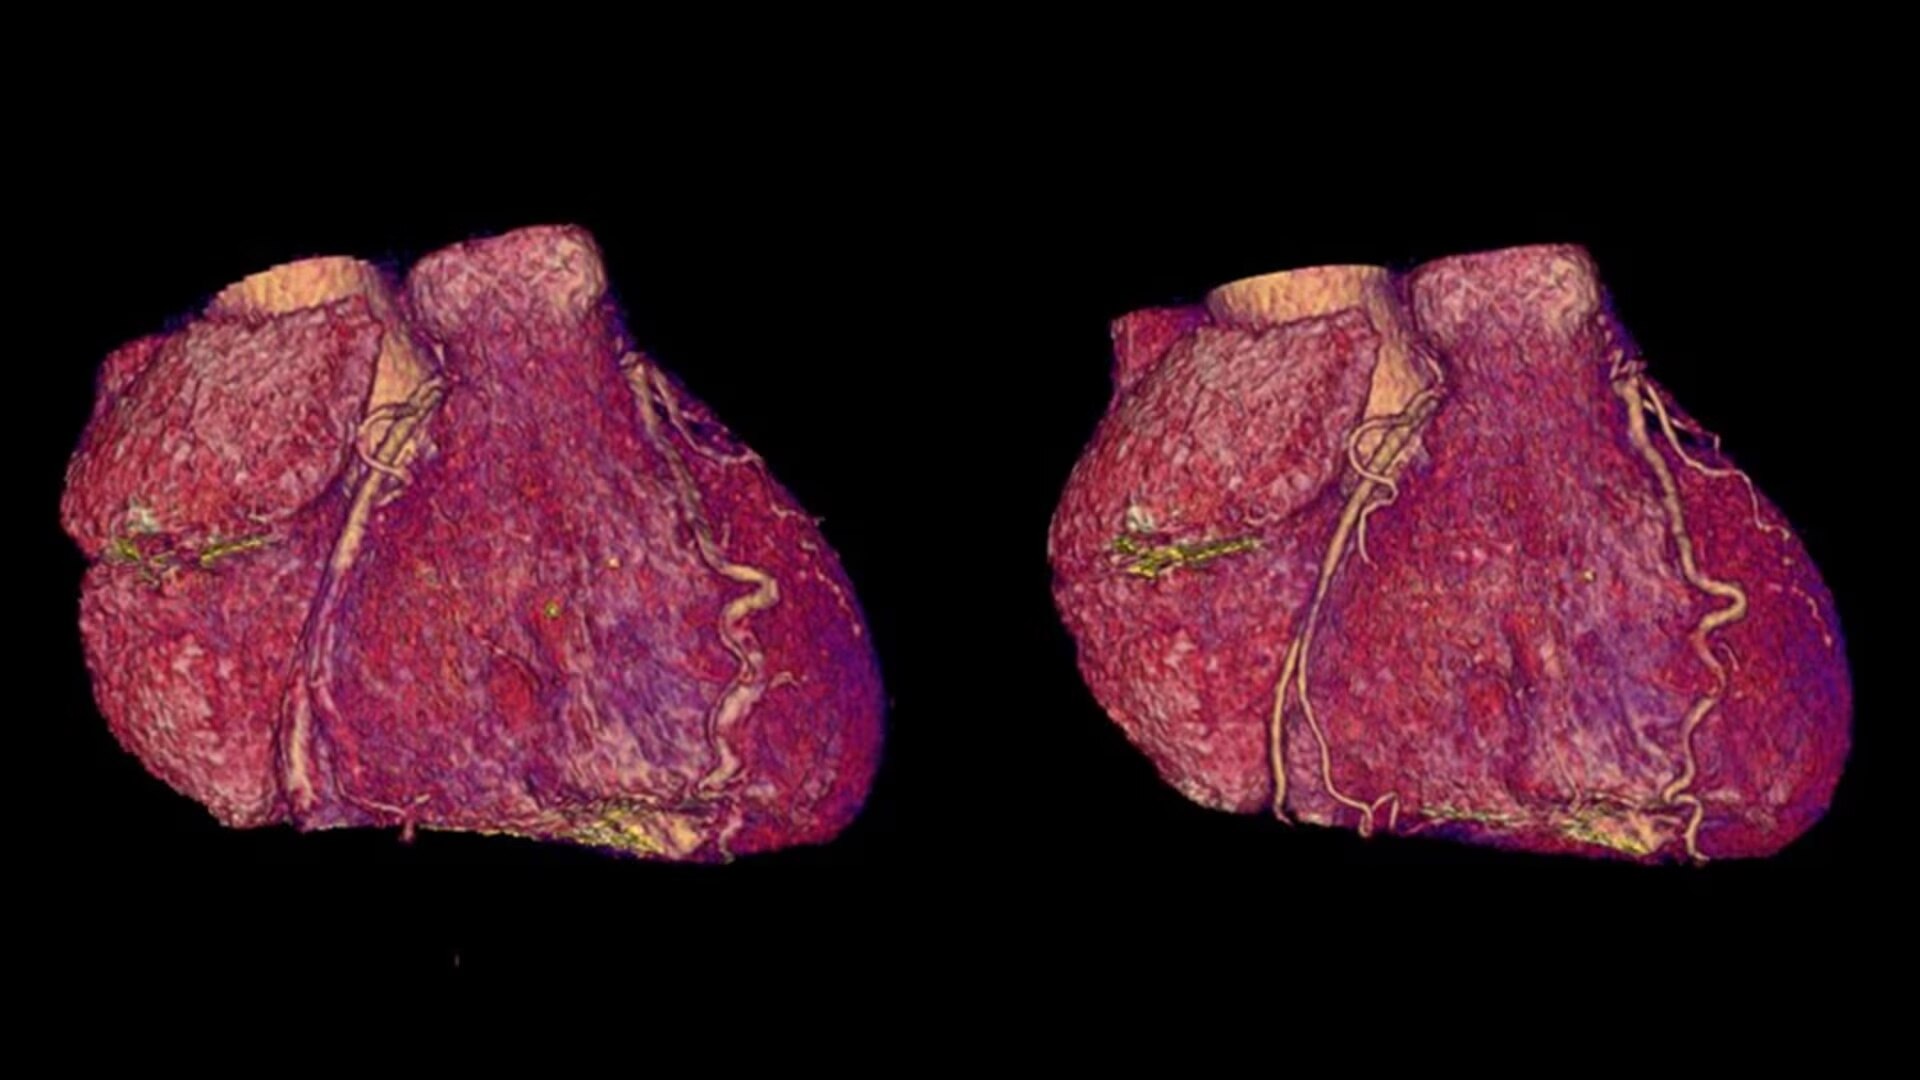

SnapShot Freeze 2

Intelligent and automated whole-heart motion correction for enhanced Cardiac CT imaging.

Motion correction

6x reduction in motion artifacts1

Temporal resolution

19.5 msec effective temporal resolution at 0.23s/rotation gantry speed2